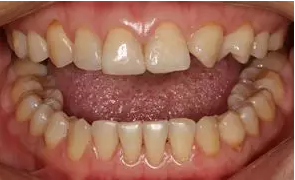

術前全牙弓咬合照

病例分享|復合樹脂微創(chuàng)美學修復關閉上前牙間隙